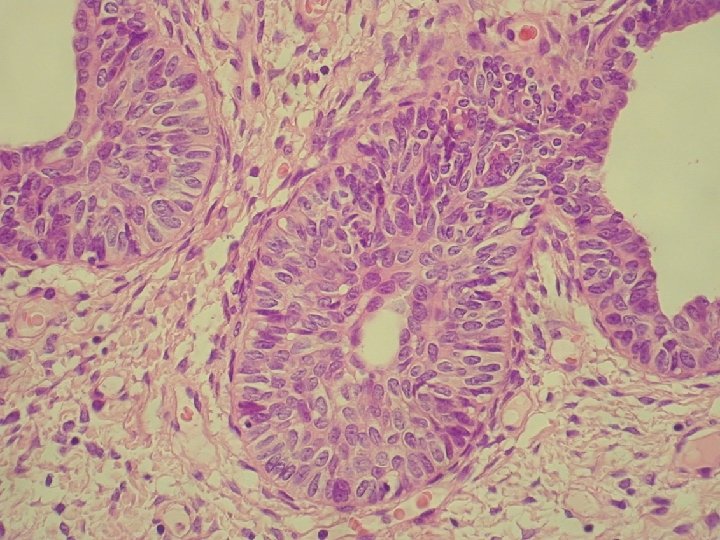

Klinicky: chronická abdominálna bolesť, dyspareunia polypoidné hemoragické masy Ø Histologicky: prezencia tubálneho epitelu s

Klinicky: chronická abdominálna bolesť, dyspareunia polypoidné hemoragické masy Ø Histologicky: prezencia tubálneho epitelu s variabilnou architektonikou v edematóznej, prevažne fibrotickej stróme Ø glandulárne prevažne tubálne inklúzie z malých epiteloidných buniek s eozinofilnou cytoplazmou, s riasinkami, sekretorické a „peg“ cells

Ø hladkosvalové vlákna a lymfoplazmocytárny infiltrát Ø bohatá vaskularizácia v retiformnej stróme, miestami aj

Ø hladkosvalové vlákna a lymfoplazmocytárny infiltrát Ø bohatá vaskularizácia v retiformnej stróme, miestami aj myxoidnej Ø Imuno: silná desmin pozit. Ø CD 34, S-100, alfa aktin, CK, calponin negat. Ø prezentovaná reaktívna stromálna proliferácia publikovaná v dvoch „case reportoch“